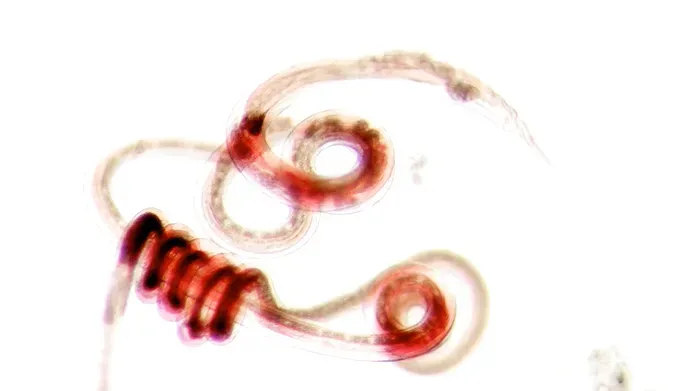

A stunted worm that has been treated with the vaccine. Credit - University of Dundee